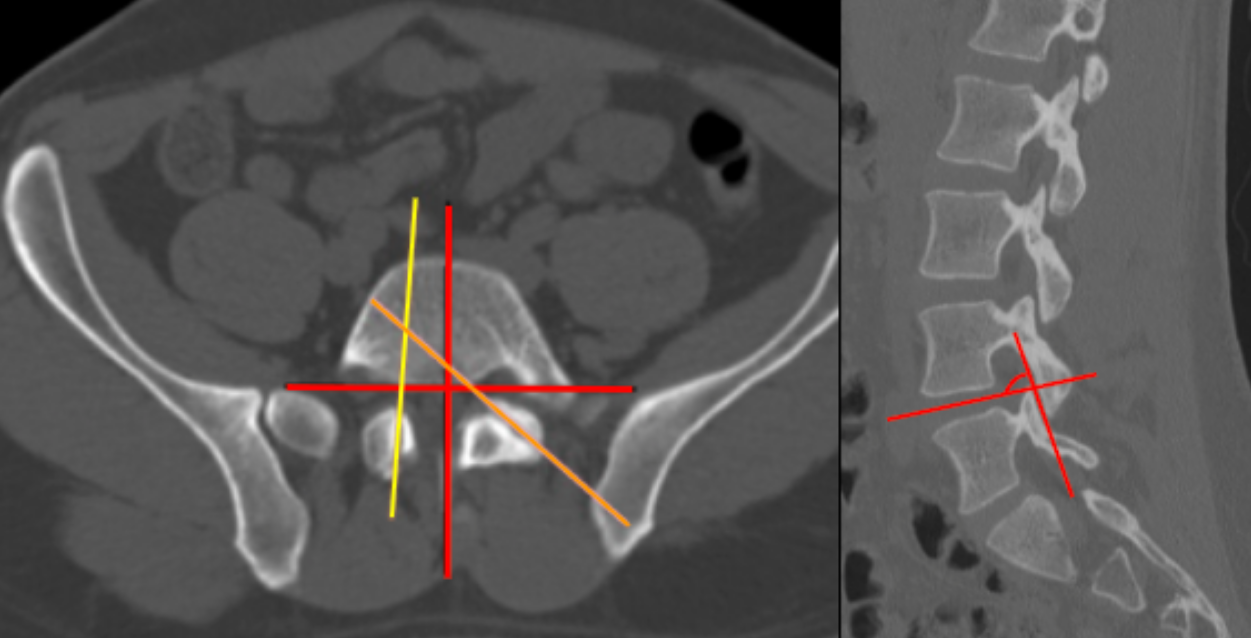

1) Description of Measurement

Facet joint orientation describes the angular relationship of the lumbar zygapophyseal joints relative to the midsagittal plane. Orientation reflects biomechanical behavior of the motion segment:

Facet tropism represents asymmetry between right and left facet joint angles, causing uneven motion and asymmetric load transfer. According to the attached study, facet tropism is defined as a bilateral difference > 10° in the axial plane. A smaller angle indicates sagittal orientation, while a larger angle indicates coronal orientation.

2) Instructions to Measure

• Select the axial CT slice that bisects the intervertebral disc at the level of interest.

• For each facet joint:

• Draw a facet line connecting the anteromedial and posterolateral edges of the articular surface.

• Draw a midsagittal reference line perpendicular to the posterior vertebral body wall through the base of the spinous process.

• Measure the facet joint angle between the facet line and the midsagittal reference line for:

• Right facet

• Left facet

• Select the parasagittal CT slice that shows the facet joint of interest

• Draw a line between the anterosuperior edge and posteroinferior edge of each facet joint

• Draw another line which bisects the intervertebral disc of the corresponding level

• Measure the facet joint angle between the facet line and the intervertebral disc line